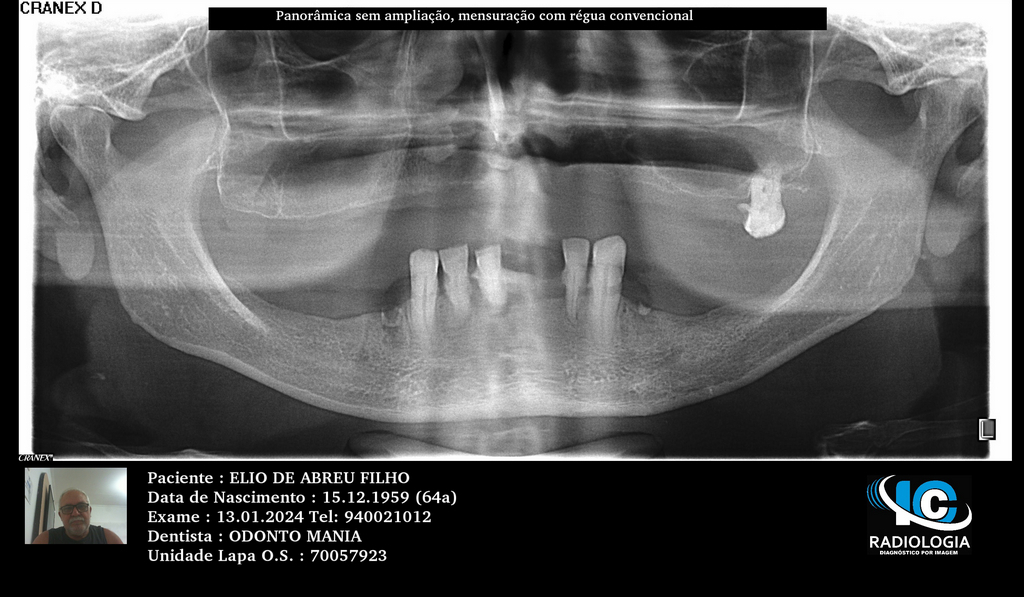

PRÓTESE TOTAL FIXA EM IMPLANTES

E.D.A.F